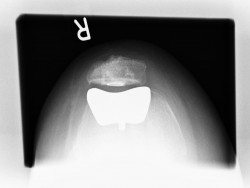

Nachdem ein OP-Termin mit Ihnen vereinbart wurde, wird anhand von speziell in unserer Praxis angefertigten Röntgenbildern mit Maßstab individuell das Implantat mit Hilfe eines speziellen Prothesenplanungsprogrammes geplant.

Teilgelenkersatz des Kniescheibengleitlagers („Femoropatellarersatz“)

Bei vielen Patienten ist nur der Anteil hinter der Kniescheibe von einem fortgeschrittenen Verschleiß betroffen. Hier gibt es die Möglichkeit einen Ersatz dieser Gelenkflächen hinter der Kniescheibe und korrespondierend dazu das Gleitlager für die Kniescheibe am Oberschenkel zu ersetzen. Hierbei bleiben sämtliche Bänder, Menisken sowie der innere und äußere Gelenkanteil intakt.